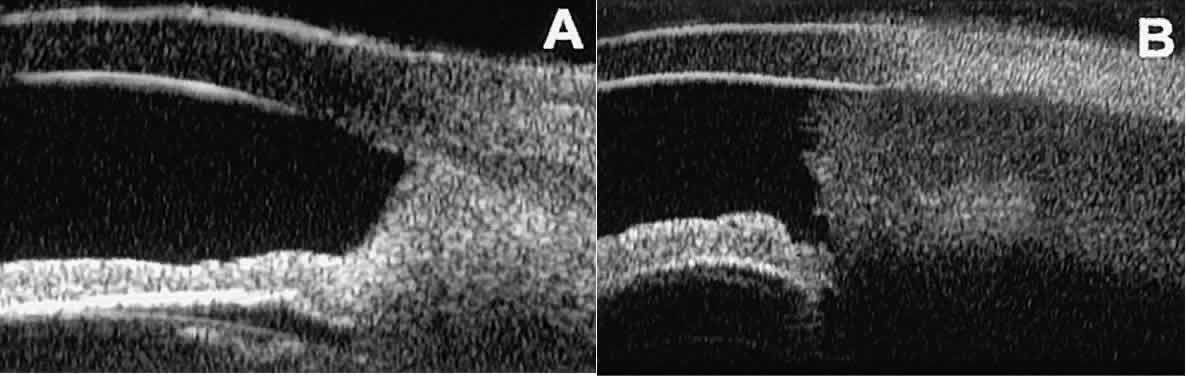

After any type of glaucoma filtering surgery,10 UBM can be used to detect and evaluate the extent of postoperative complications such as ciliochoroidal effusion and cyclodialysis.3,4 In ciliochoroidal effusion (Fig. 13A), UBM shows the ciliary body to be edematous and separated from the sclera by a sonolucent collection of supraciliary fluid. Many ciliochoroidal effusions that are too limited in extent to be detectable by indirect ophthalmoscopy and slit lamp biomicroscopy can be imaged by UBM. In cyclodialysis (see Fig. 13B), UBM shows a well-defined separation between the uveal tissue and the sclera in the region of the scleral spur. The width of the cleft is usually assessed best by means of limbus-concentric images through the region of interest.

Fig. 13. Complications of intraocular surgery. A. Postoperative ciliochoroidal effusion appears as slitlike spaces filled with serous fluid posterior to scleral spur. B. Postoperative cyclodialysis appears as complete separation of iris and ciliary body from sclera in region of scleral spur.

Ultrasound biomicroscopy appears to be helpful postoperatively in determining the extent of postoperative complications of cataract surgery such as serous choroidal detachment (see Fig. 13A), iridocapsular adhesion (Fig. 19A), postoperative hyphema (see Fig. 19B), stripping of Descemet's membrane (see Fig. 19C), and wound gaping (see Fig. 19D).

Fig. 19. Complications of cataract surgery revealed by UBM. A. Capsular adhesion to midzone of iris. B. Postoperative hyphema. Clot appears denser than aqueous with suspended blood cells. C. Stripping of Descemet's membrane. D. Wound gape.